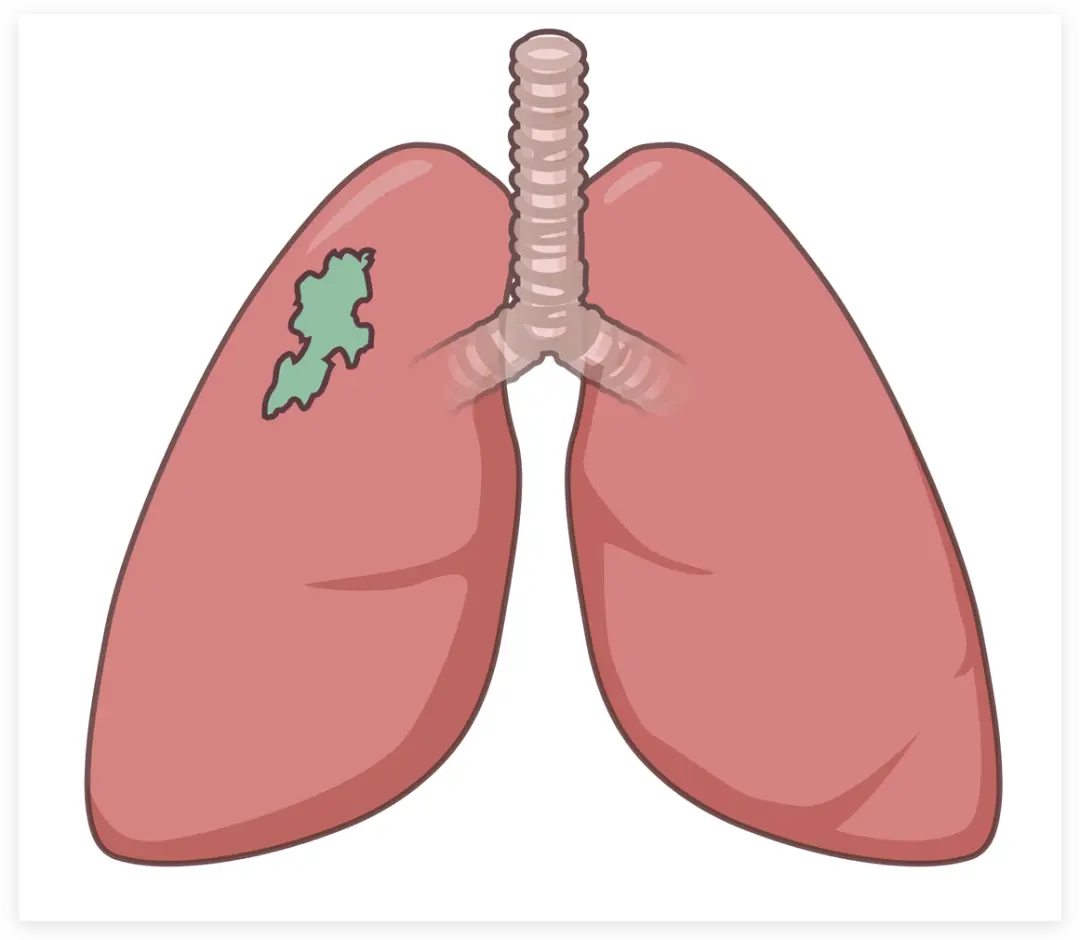

画出肺的外轮廓

上色

加上暗部和绿色区块